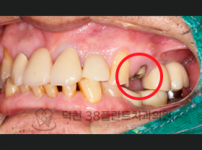

치료전후